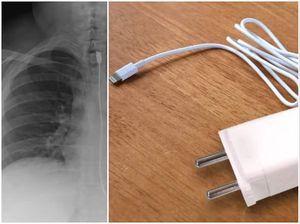

Pria India Sakit Perut 2 Tahun, Ternyata Ada 60 Barang 'Nyangkut' di Perut

Seorang pria India mengeluhkan sakit perut selama dua tahun. Saat dicek, ternyata ada sekitar 60 barang yang ditemukan dalam perutnya. Kok bisa? Ini kisahnya.